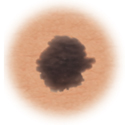

Normal mole.

This is a normal mole.

Moles (nevi)

Small skin marks caused by pigment-producing cells in the skin. Moles can be flat or raised, smooth or rough, and some contain hair. Most moles are dark brown or black, but some are skin-colored or yellowish. Moles can change over time and often respond to hormonal changes.